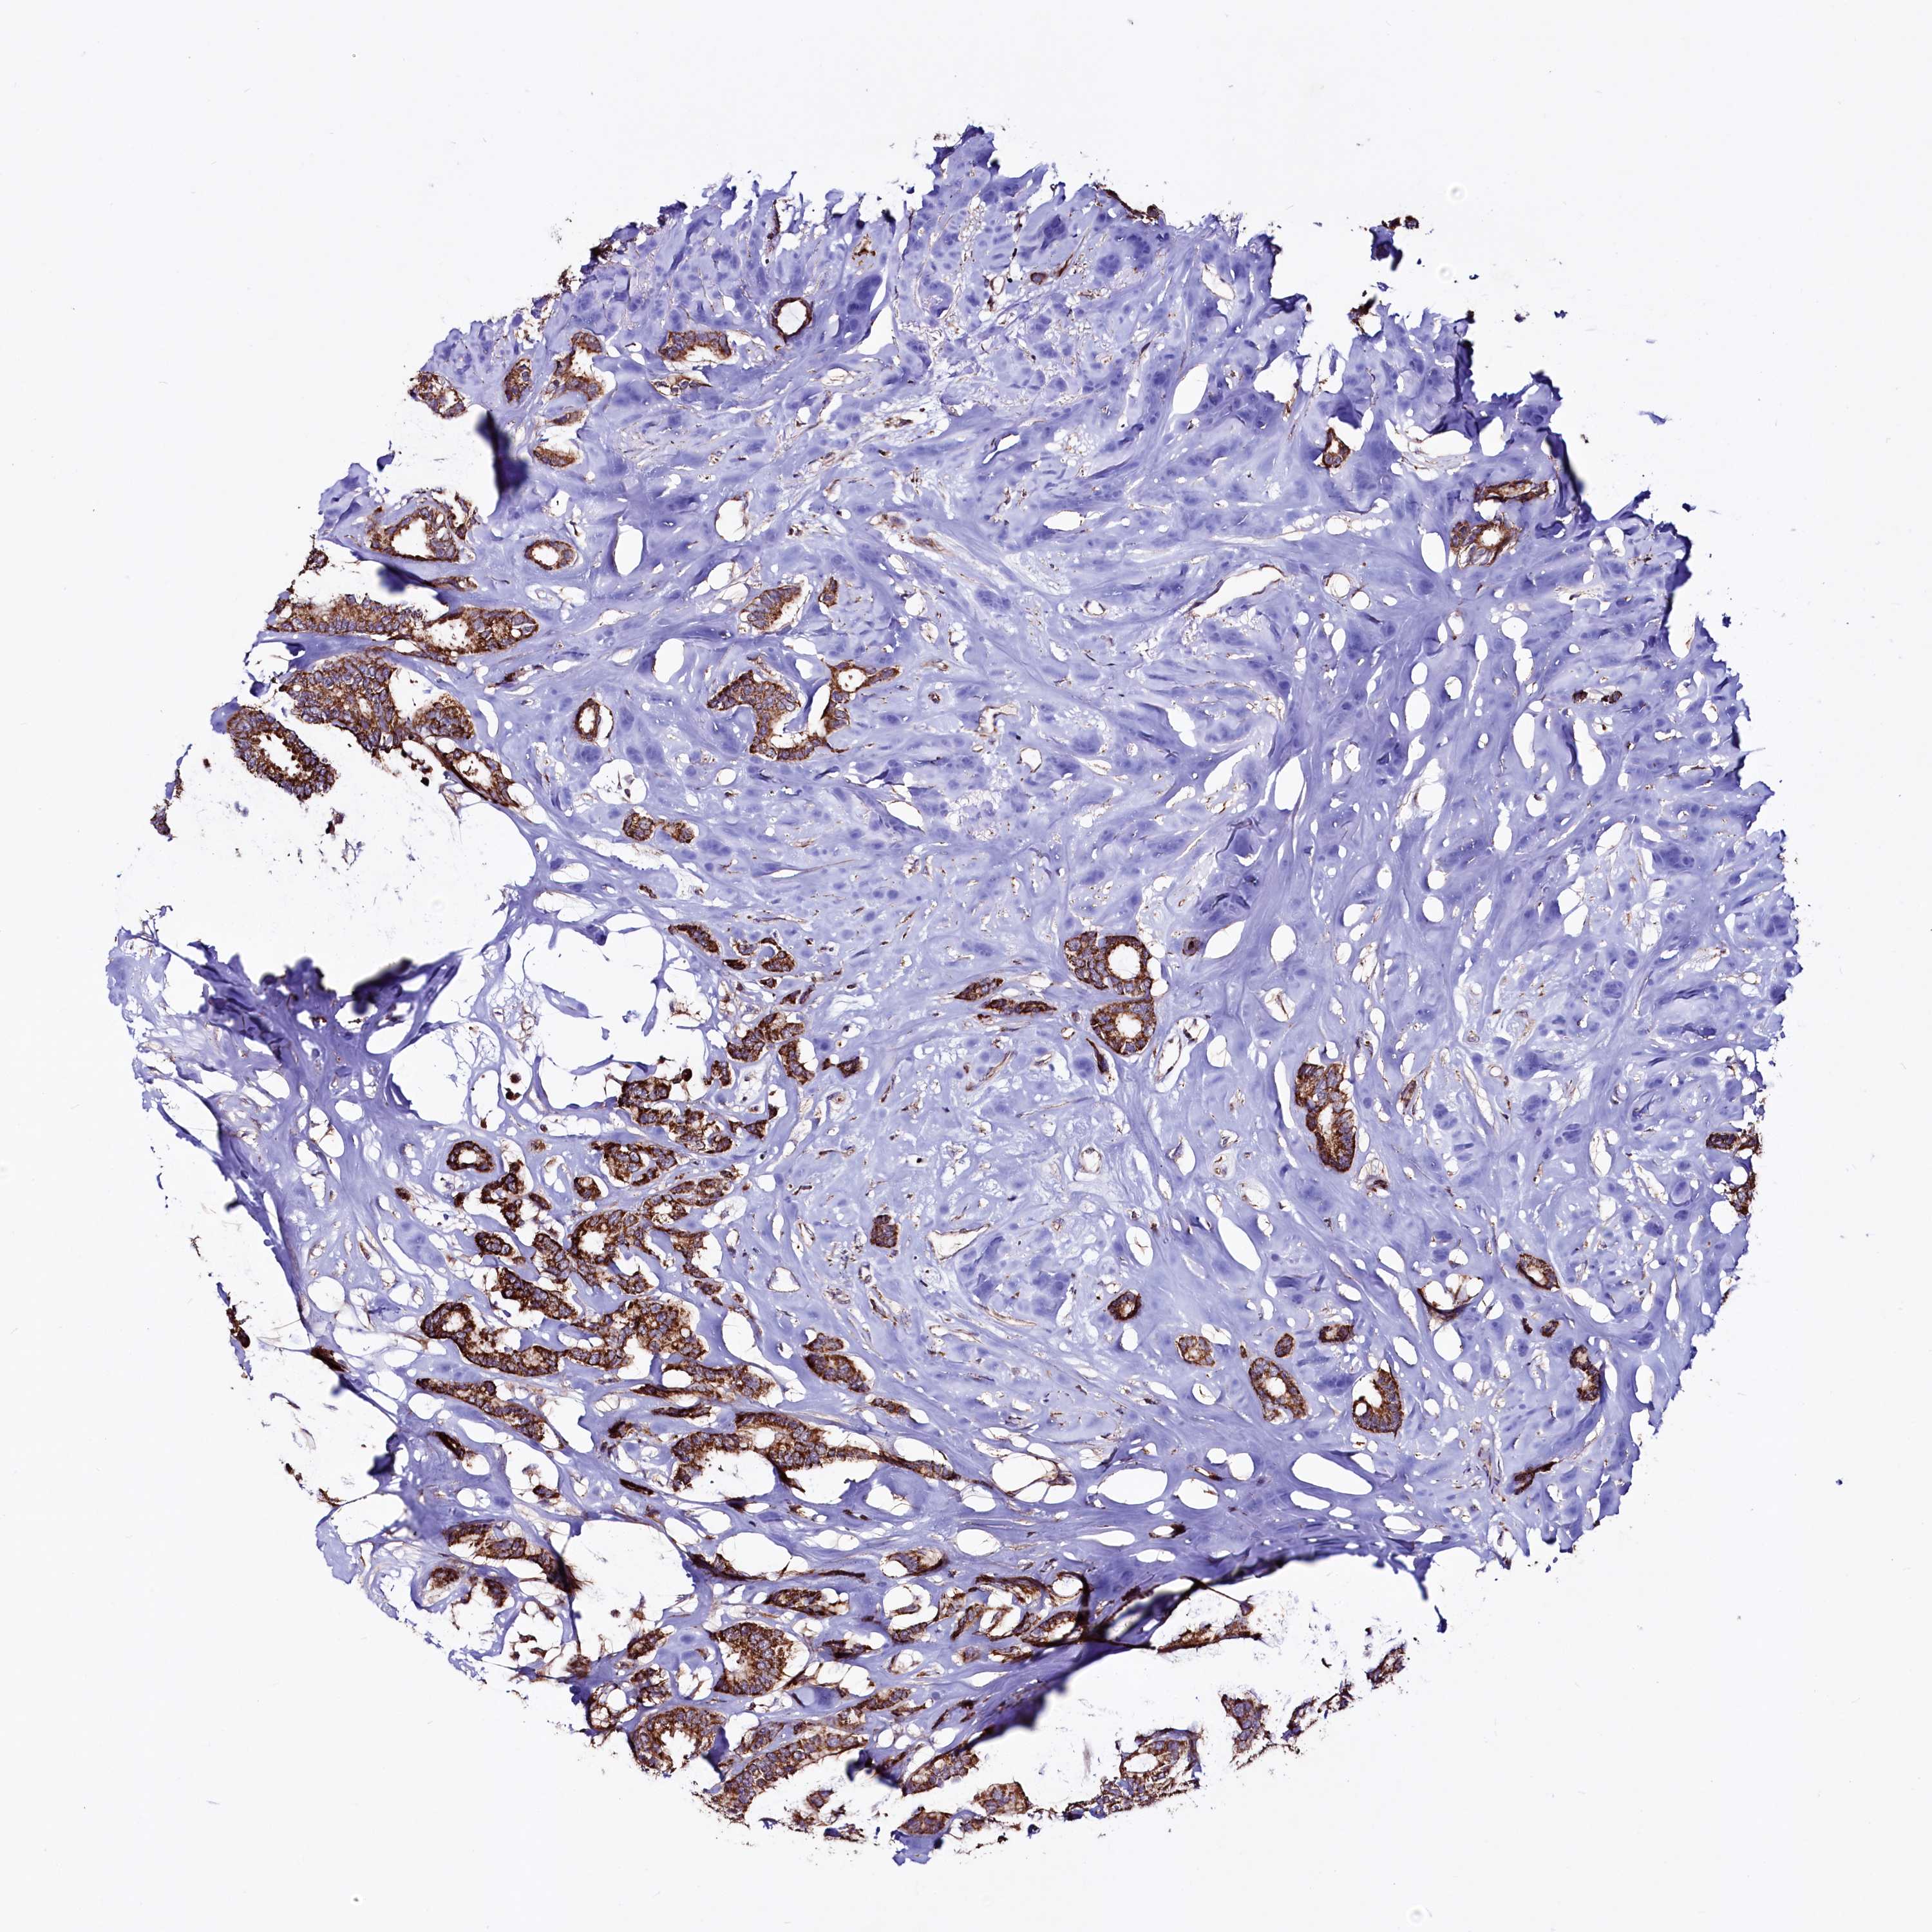

BRCA TCGA BRCA VALIDATION PROTEIN EXPRESSION